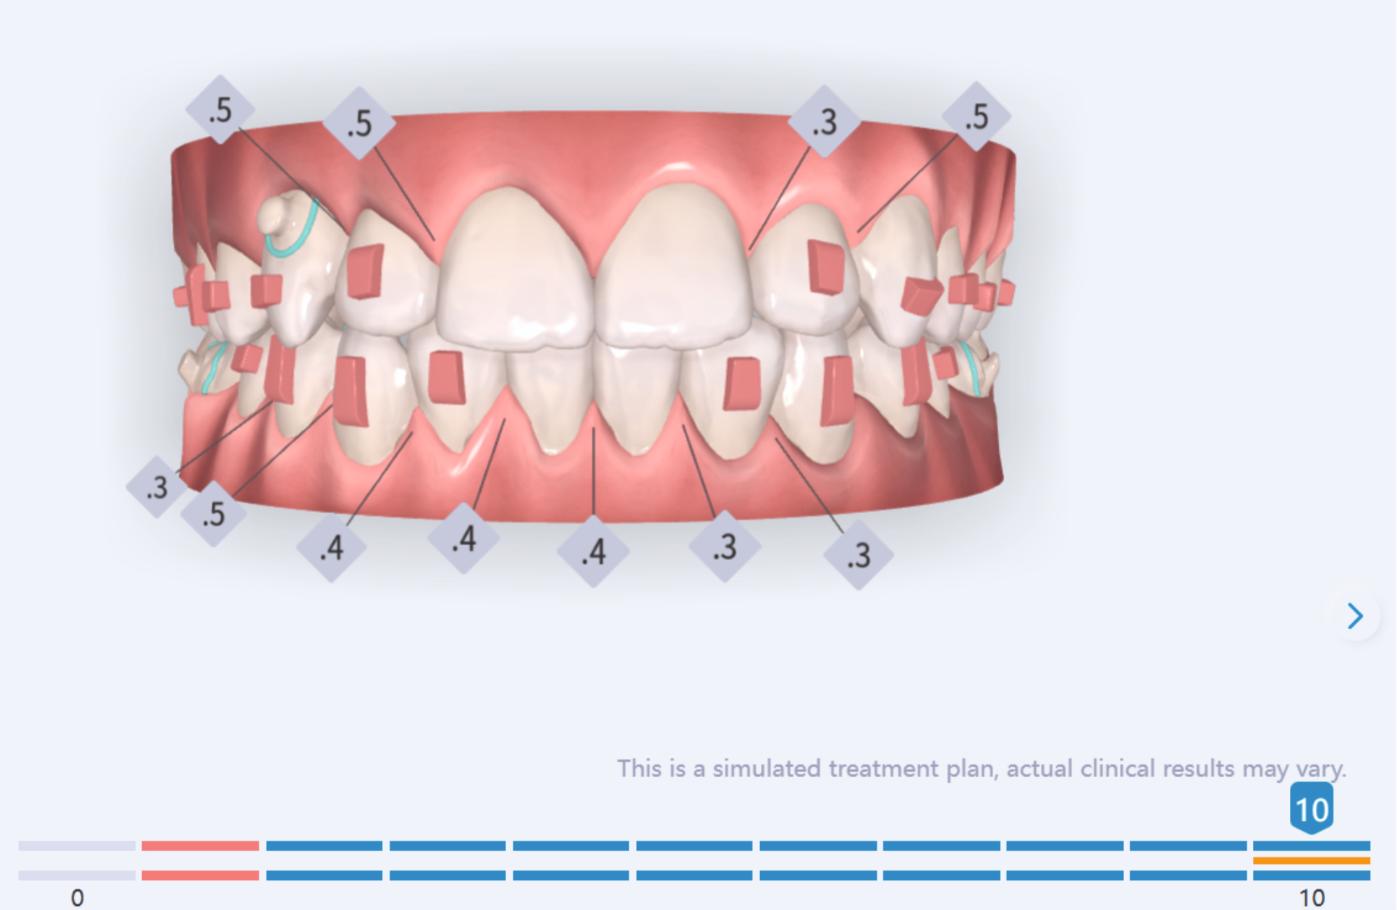

Treatment details

In the upper arch, the main goal will be to correct the Class II malocclusion by distalizing the upper posterior teeth in order to resolve crowding without proinclining the incisors. This movement will be accompanied by an asymmetric “bite jump” of 1 mm, which will help improve the skeletal Class II discrepancy, promoting mandibular projection, especially considering that the patient is still in the growth phase. Additionally, bilateral and symmetric expansion will be planned until a torque of 0° is achieved, allowing for proper transverse alignment and greater stability of the final result. Lingual button cutouts will be placed on teeth 14 and 24 to facilitate the required movements. To optimize control and retention, vertical mesial beveled attachments, as large as possible, will be placed on the premolars and molars, as well as on teeth 12 and 22, reinforcing the mechanics in the anterior sector. The inclination of the central incisors 11 and 21 will be corrected according to the visual reference provided in the clinical image. Furthermore, it will be necessary to center the upper midline by shifting it 0.5 mm to the left to achieve greater aesthetic symmetry. As for the lower arch, treatment will begin with a phase of expansion and derotation of the posterior teeth, which will set the stage for subsequent movements in the anterior sector. Once this goal is achieved, alignment of the teeth from canine to canine will proceed, aiming to minimize anterior interproximal reduction (IPR) and avoid unnecessary round- tripping movements of the incisors. Vestibular button cutouts will be made on teeth 36 and 46, while teeth 37 and 47 will have horizontal attachments that will serve as anchorage to ensure stability during treatment.

Treatment setup